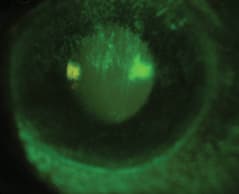

Figure 1 was taken after the patient had worn the LDS lenses for about four hours. Antibiotic ointment applied to the lids and cornea was not successful. We felt that the fit of the lenses could be improved.

Figure 1. Patient's cornea following wear of a large-diameter scleral lens for four hours.